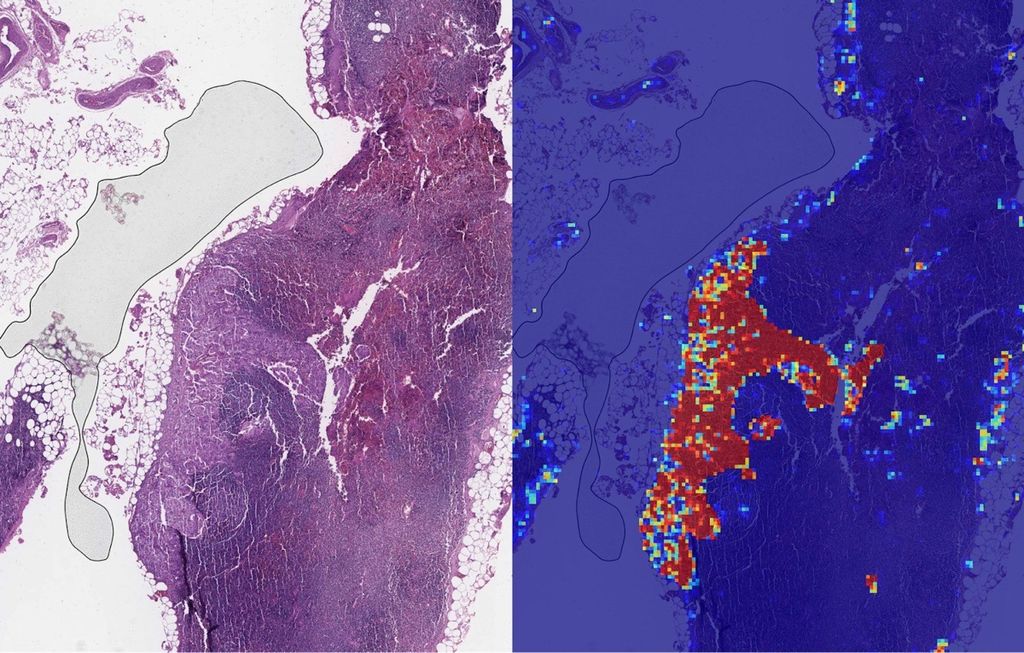

Lenf Nodu Asistanı (LYNA) olarak adlandırılan algoritmayı geliştiren Google’ın araştırmacıları, iki patoloji slaytı setini kullanarak tümörlerin karakteristik özelliklerinin tespitini mümkün hâle getirdi. Bu sistemin kanserin yayılmasını çok farklı koşullarda görebildiği ifade edildi.

Google’ın algoritmasının kanserli ve kansersiz slaytlar arasındaki farkı yüzde 99 oranında doğru tespit edebildiği belirtilirken, sistemin insan gözünden kaçabilecek küçük yayılmaları bile fark edebildiğinin altı çizildi.

LYNA’nın patoloji uzmanları tarafından destekleyici bir araç olarak kullanıldığında çok daha verimli bir araca dönüştüğünü vurgulayan Google, sistemin teşhis simülasyonlarıyla uzmanların işini kolaylaştırdığını belirtti. Küçük sıçramaların tespitindeki hata payını hatırı sayılır ölçüde azaltan LYNA ile inceleme süresinin de 1 dakikaya indiği ifade edildi.